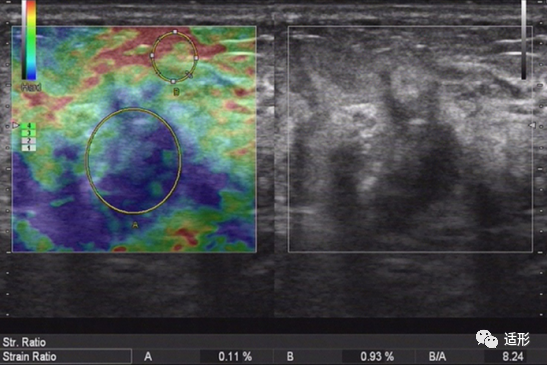

NML的弹性表现与病变的病理类型有关。恶性NML的病变硬度高于良性NML。根据病变应变式弹性成像(SE)的弹性图像表现,可利用5分评分法来评价NML的良恶性。良性NML病变较恶性NML病变软,评分多为1-3分(图1)。恶性NML较良性NML病变硬,评分多为4-5分(图2) 。结合常规超声与5分评分法评价NML,诊断恶性NML的准确性可达83.1%。另外,也可应用病变组织与皮下脂肪组织的弹性应变率比值来鉴别NML良恶性。Qu等以4.07为应变率比值截断值时,其诊断恶性NML的准确率可达95.5%。

图2. 60岁女性,超声提示乳腺内非肿块型病变,呈低回声。弹性评分(右侧)为5分,应变率比值为8.24. 病理:浸润性导管癌